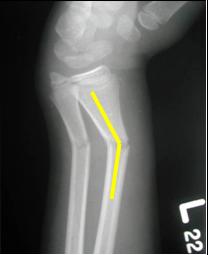

Radial and ulnar fractures demonstrate

posterior (or dorsal) angulation

Posterior/

dorsal

Anterior/

ventral